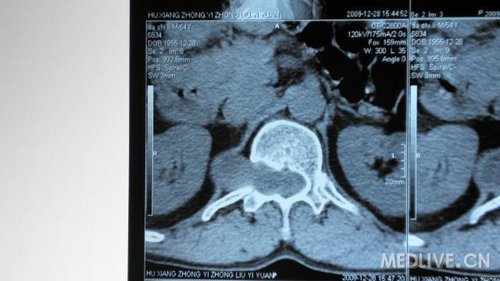

http://webres.medlive.cn/upload/000/030/214

还有CT片